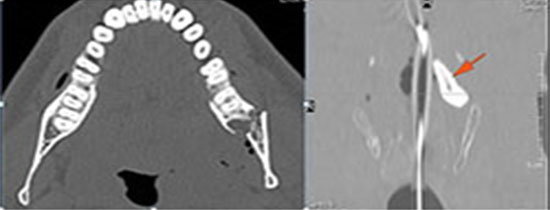

Blunt trauma to the face.Exam

Non contrast CT of the maxillofacial region was obtained with 0.5-1.0 mm thick sections in the axial plane and reformatted 3D and/or in the coronal and sagittal planes and viewed interactively in 3 dimensions at the computer work station.